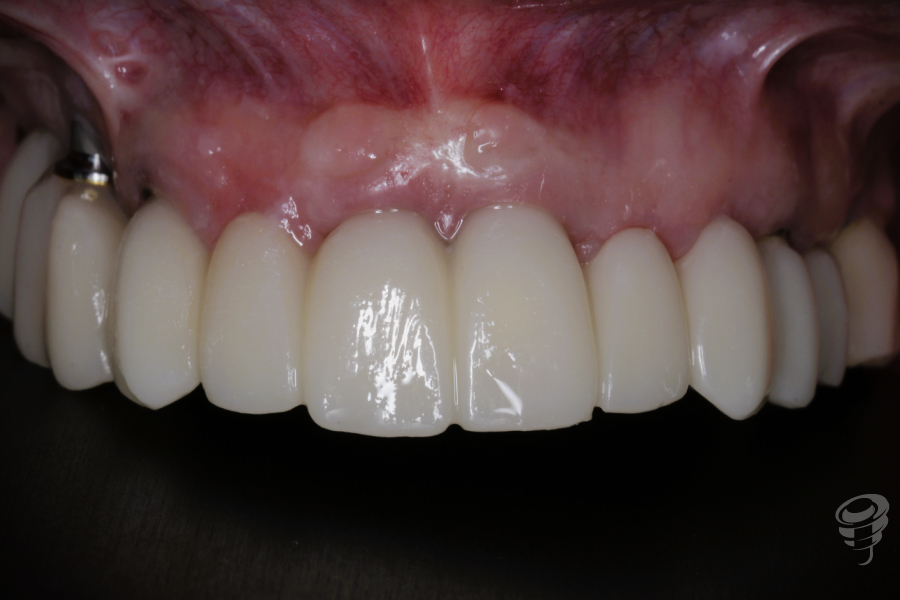

Resultado

Resultado de los perfiles de emergencia, situación estética gingival y protética de un PMMA que será el paso justamente anterior a la prótesis definitiva que se realizará en Zirconio monolítico.